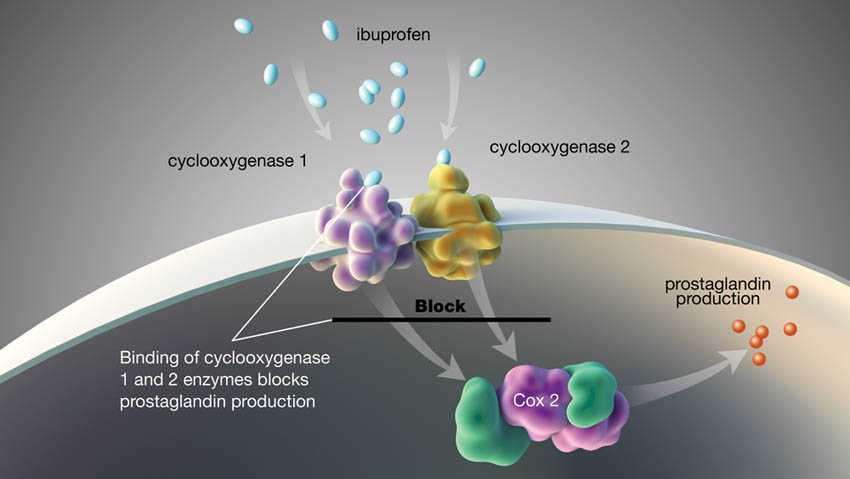

Παρόλο που η οριστική θεραπεία των οδοντικών καταστάσεων θα πρέπει να αποτελεί τον κύριο στόχο της παροχής περίθαλψης σε ασθενείς που πονούν και η τοπική αναισθησία μπορεί να βοηθήσει σε αυτό, μπορεί να είναι πλεονεκτική ή απαραίτητη η διαχείριση του πόνου με φάρμακα. Τα μη συνταγογραφούμενα φάρμακα που είναι χρήσιμα για την αντιμετώπιση του πόνου περιλαμβάνουν τόσο τα μη στεροειδή αντιφλεγμονώδη φάρμακα (ΜΣΑΦ) όσο και την ακεταμινοφαίνη (παρακεταμόλη). Η ιβουπροφαίνη είναι το πλέον μελετημένο ΜΣΑΦ για τον οδοντικό πόνο, πιθανώς λόγω του υψηλής ασφάλειας προφίλ του φαρμάκου αυτού και έχει βολική δοσολογία. Η ιβουπροφαίνη θεραπεύει τη φλεγμονή και εξασφαλίζει τη δράση της αποκλείοντας τα ένζυμα κυκλοοξυγενάση 1 και κυκλοοξυγενάση 2, τα οποία εμποδίζουν την παραγωγή προσταγλανδινών, οι οποίες εμπλέκονται στη μετάδοση του πόνου (Εικ. 3). Σύμφωνα με τον κατασκευαστή, η μέγιστη συνιστώμενη δόση ιβουπροφαίνης είναι 3.200 mg/ημέρα. Η ακεταμινοφαίνη έχει διπλή δράση: αναστέλλει τη σύνθεση της προσταγλανδίνης περιφερικά και δρα κεντρικά αλληλεπιδρώντας με τους κανναβινοειδείς και σερετονεργικούς υποδοχείς (Εικ. 4). Σύμφωνα με τον κατασκευαστή, η μέγιστη συνιστώμενη δόση ακεταμινοφαίνης είναι 3.000 mg/ημέρα.

ιβουπροφαίνη

κυκλοοξυγενάση 1

κυκλοοξυγενάση 2

Η δέσμευση των ενζύμων κυκλοοξυγενάση 1 και κυκλοοξυγενάση 2 αποκλείει την παραγωγή προσταγλανδίνης

Αποκλεισμός

παραγωγή προσταγλανδίνης